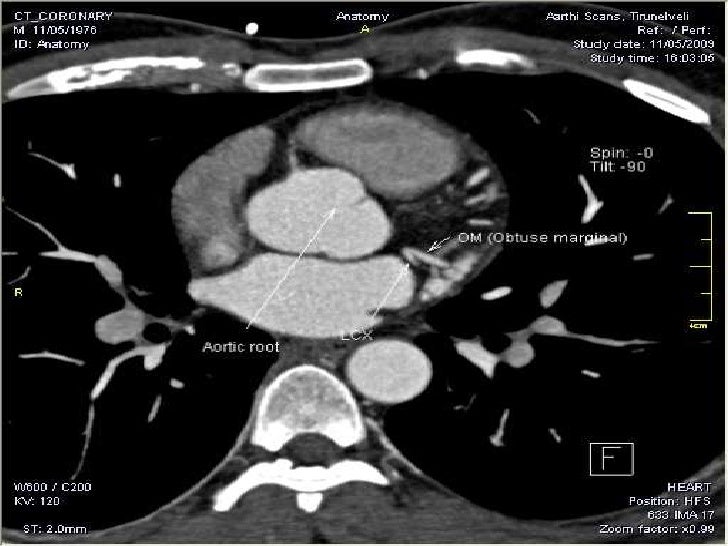

TC angiografía ateromatosis calcificada de arterias coronarias (imagen... Download Scientific

Tc Angio Coronariana; O que é? Através de uma tomografia computadorizada do coração com contraste, permite detectar e a quantificar entupimentos nas artérias coronárias (vasos responsáveis pela irrigação sanguínea do coração, e que quando obstruídos podem levar ao infarto agudo do miocárdio). De maneira mais simples e minimamente.

Una angiografía coronaria por tomografía computarizada es una prueba por imágenes para observar las arterias que suministran sangre al corazón. La angiografía coronaria por tomografía computarizada utiliza un potente equipo de rayos X para producir imágenes del corazón y sus vasos sanguíneos. Esta prueba se usa para diagnosticar.